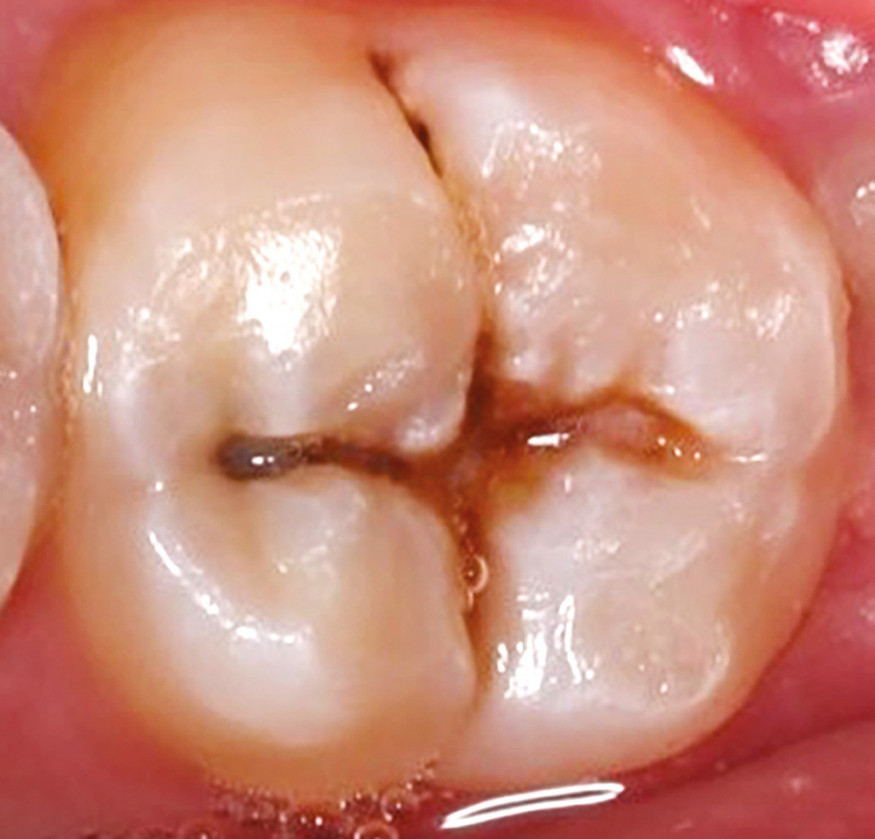

Aujourd’hui, malgré certaines publications internationales, ce procédé reste peu connu. Avec une méthodologie particulièrement simple et aisée, il consiste à enregistrer sous la forme d’un isomoulage la surface occlusale d’une dent cariée avant toute préparation de celle-ci. L’isomoulage est ensuite appliqué à la surface du composite de restauration avant sa photopolymérisation pour lui imposer la forme originelle de la dent. De fait, la réalisation de la technique implique initialement que la lésion carieuse ne délabre pas l’anatomie de la surface occlusale (fig. 1).